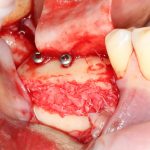

Кстати, обрати внимание на ширину альвеолярного гребня (левая картинка). Она чуть меньше 3 мм. Это объясняет, почему я засомневался в возможности установки имплантатов одновременно с остеопластикой. Понятно и без КЛКТ.

Наперво, мне нужно удалить разрушенный зуб и получить костный аутотрансплантат.

Возвращаемся к основной операционной области. Еще раз посмотрим на альвеолярный гребень, поофигеваем от его ширины и моих грандиозных планов: